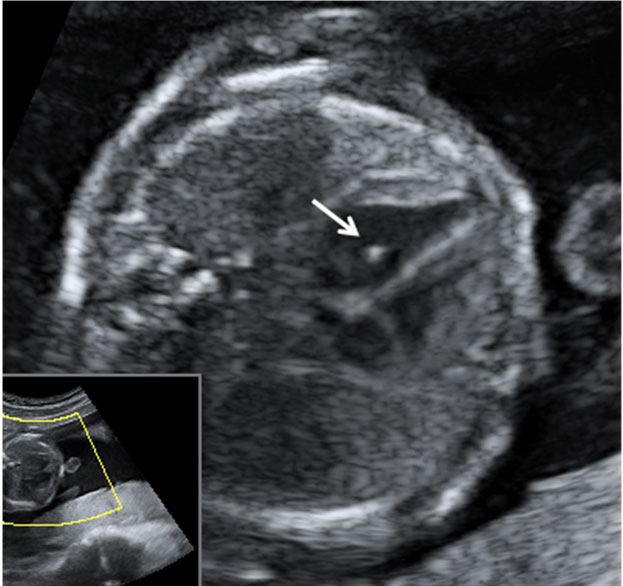

Ecografía Embarazo 2D y 3D Semana 20 - MALFORMACIONES FETALES